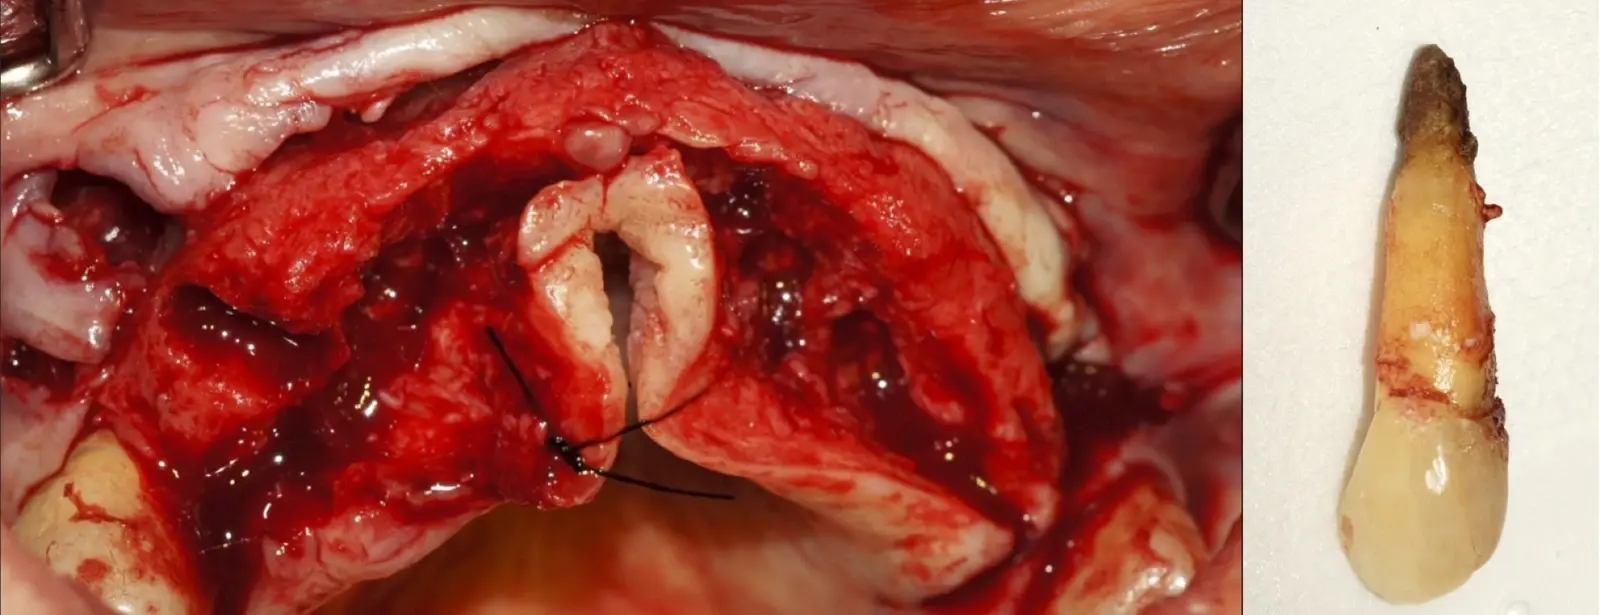

El procedimiento se inicia colocando anestesia y elevando un colgajo mucoperióstico a espesor completo y exponiendo la zona. En seguida se realiza la enucleación de la lesión, eliminando o creando una ventana en la lámina cortical que contiene el área del ápice.

El procedimiento se inicia colocando anestesia y elevando un colgajo mucoperióstico a espesor completo3 (incisión semilunar o intrasurcular con/sin protección papilar) y exponiendo la zona. En seguida se realiza la enucleación de la lesión, eliminando16 o creando una ventana17 en la lámina cortical que contiene el área del ápice; este retiro óseo se realiza con los insertos de forma aplanada dentada o inserto con cobertura diamantada plano o redondo, recordando ser lo más conservador posible (Figura 5).

Una vez limpia la zona apical, se corrobora la integridad de la raíz y se evalúa el grado de extensión de la lesión. Si el defecto óseo es pequeño, se procede a realizar la preparación del conducto y obturación retrógrada de ser el caso. Si el defecto óseo es de gran tamaño e inaccesible a los insertos, se procede a realizar un corte de por lo menos 3 mm de ápice radicular conteniendo los posibles conductos aún infectados11 empleando habitualmente insertos de borde aserrado con/sin marcas de medición para un trabajo seguro7 (Figura 7).

Si el tratamiento de conducto previo es reciente y no está contaminado, se procede al cierre de la herida, previa evaluación de la necesidad de material de regeneración ósea en la zona. Si el tratamiento de conducto previo es de larga data y se encuentra contaminado, se procede a la preparación apical de la zona con los kits de insertos endodónticos, a una profundidad de 3 a 4 mm19 y mediante un movimiento vertical vibratorio constante sin pulsaciones que puedan causar microgrietas en la superficie.20 Los insertos especializados poseen diferentes angulaciones y configuraciones, lo que aporta versatilidad al proceso. La conformación más usada es la del inserto angulado de extremo troncocónico sin o con superficie diamantada con grano de 30 um en los milímetros finales. Tiene como función principal la limpieza y conformación del canal (Figura 9).

Para la obturación retrograda, el sellador más usado es el agregado de trióxido mineral (MTA)21 por sus propiedades hidrofílicas y de biocompatibilidad que favorece la neoformación ósea.3 Luego de la desinfección y secado, se realiza la obturación-compactación de rutina y se culmina con la reposición de los tejidos gingivales a través de puntos de sutura (Figura 10).